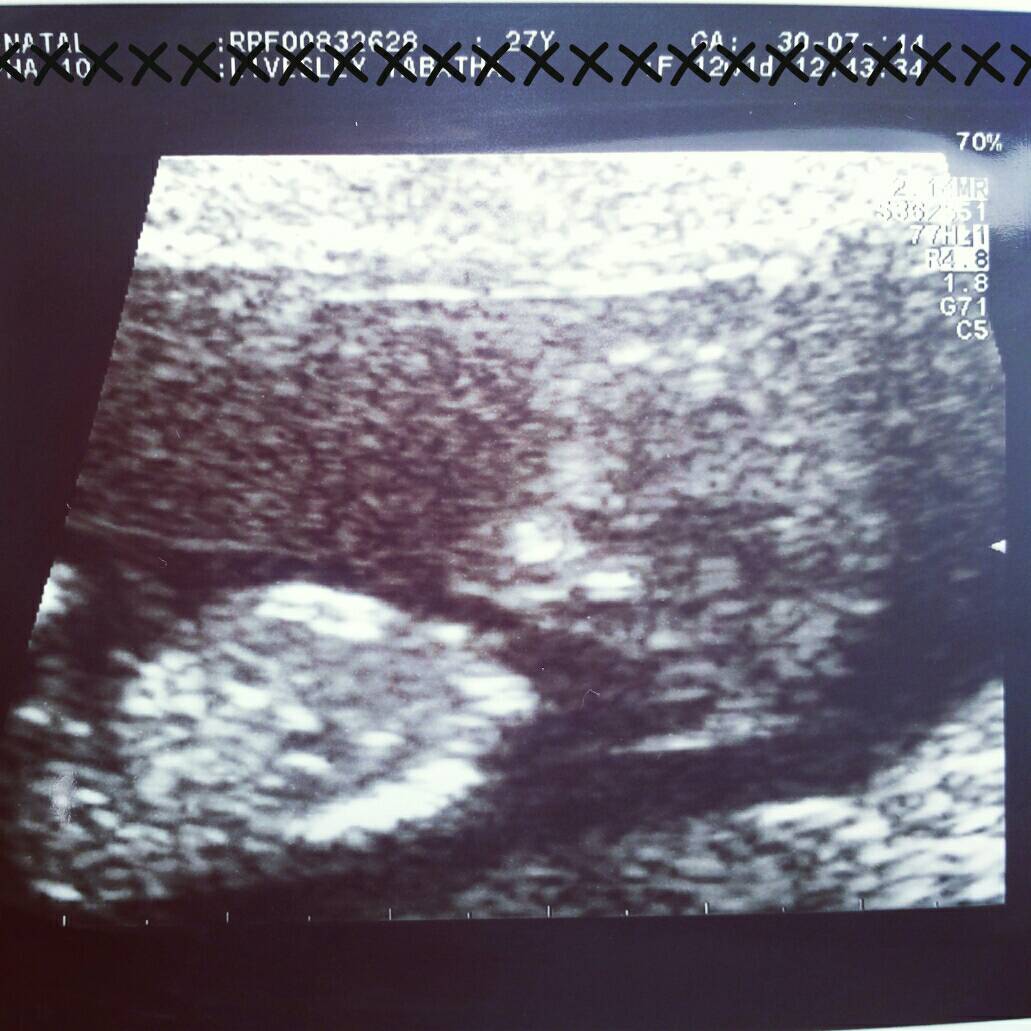

You All Guessed Boy by 100% & MaterniT21 Blood Test Revealed...GIRL!!:ttcgirl:

12wks 6days....

MaterniT21 Blood Test Revealed...GIRL!!!!